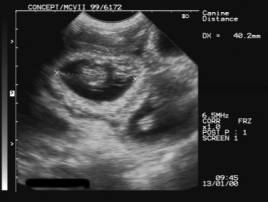

ULTRASOUND PREGNANCY DIAGNOSIS

Foetal heartbeats - day 42 Foetal sacs – day 28